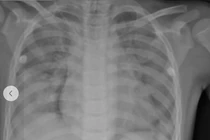

Tại Khoa Cấp cứu, bệnh nhi G.B nhập viện trong tình trạng hôn mê sâu, điểm Glasgow chỉ 5–6 điểm, đồng tử hai bên giãn tối đa, phản xạ ánh sáng yếu, mạch 80 lần/phút, phổi có nhiều rale ẩm, chi lạnh, bụng chướng hơi.

Trước tình trạng nguy kịch, bệnh nhân được hồi sức tích cực, đặt nội khí quản, thở máy, hồi sức tim phổi, truyền dịch, sưởi ấm và chuyển ngay đến Trung tâm Hồi sức tích cực để tiếp tục hồi sức chuyên sâu.

Ngay lập tức, các bác sĩ phải đặt ống nội khí quản và tiến hành hồi sức khẩn cấp. Chụp CT ngực ghi nhận tổn thương lan tỏa hai phổi, phù hợp tình trạng tổn thương phổi cấp sau đuối nước.